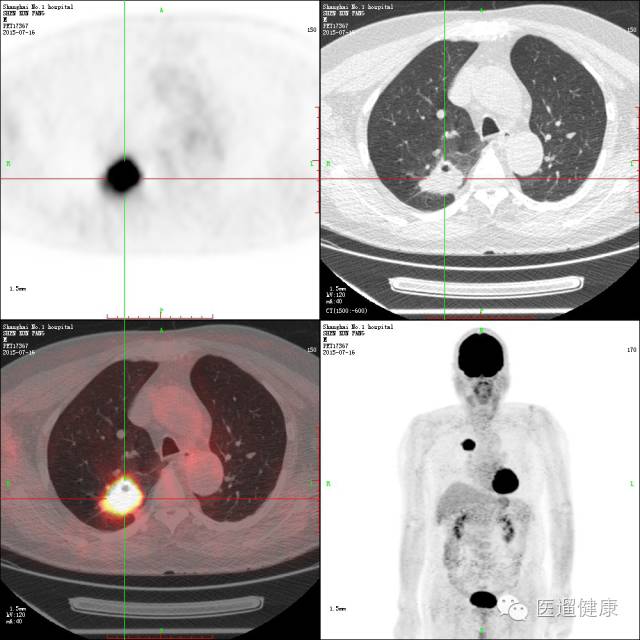

案例二、

72岁男性,首次胸部低剂量CT筛查示右肺上叶后段肿块,大小约41*26mm,不能除外肺癌。

临床医生意见:

CT片上的右肺占位是比较典型的肺癌,但是不知道有无转移灶,建议PET/CT评估。

家属意见:

开始认为PET/CT检查费昂贵,但在听取医生分析后同意进行PET/CT检查。

右肺上叶软组织肿块,葡萄糖代谢增高,考虑肺癌